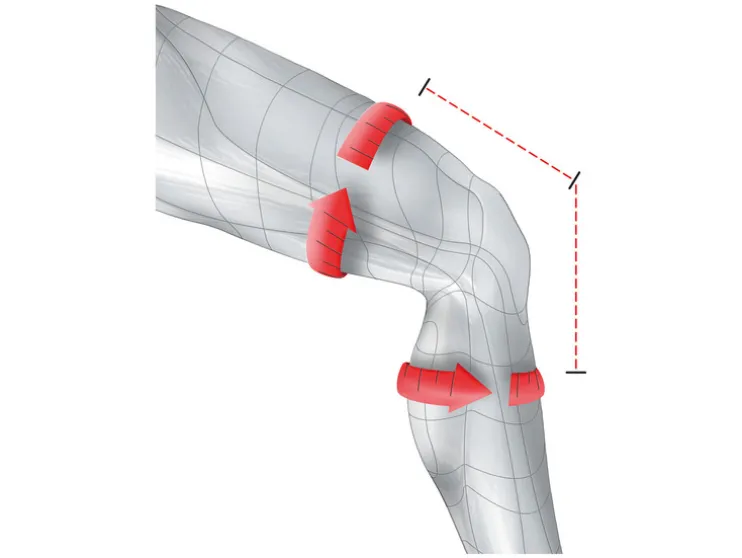

- Stabiliserende bandage voor de ondersteuning en ontlasting van het kniegewricht en de knieschijf

- Vermindert zwelling door milde compressie

- Comfortabele, ringvormige pad voor een optimale pasvorm van de knieschijf

- Met 2 zijdelingse spiraalveren